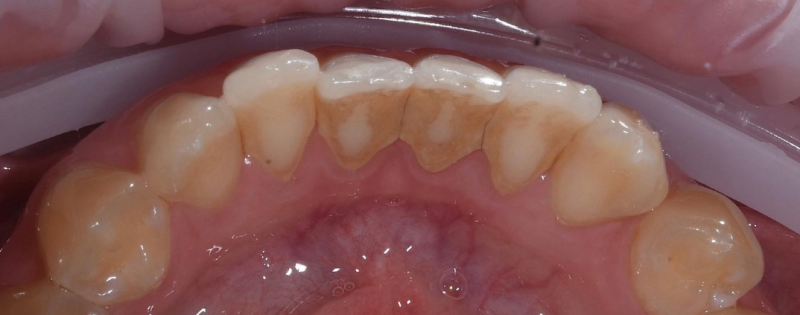

На странице представлено портфолио стоматологий Санкт-Петербурга с работами до и после профессиональной чистки зубов. В нашем портфолио собраны разные клинические случаи: от удаления незначительного налета до снятия массивного поддесневого камня. Здесь вы можете увидеть, как возвращается естественный цвет и внешний вид зубов после процедуры. Изучите результаты до и после чистки зубов, чтобы увидеть реальный эффект и выбрать клинику в Санкт-Петербурге, где профессиональная гигиена поможет вернуть зубам здоровый вид.